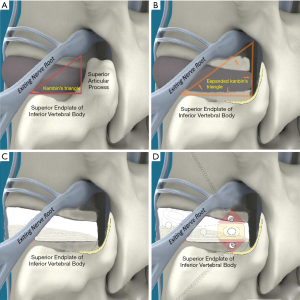

PETOFPC technique innovatively sets screws from posterior corner in lumbar spine in a regular 7.5-mm diameter channel. PETOFPC is also performed in the posterolateral transforaminal approach (Figure 18). A cylindrical sheath with an outer diameter of 7.5 mm were inserted in sequence. Through the sheath alone or the endoscope, the intervertebral disk and cartilaginous endplate were removed while confirming through percutaneous endoscopic observation that no cartilage remained. At the completion of the endplate preparation, the new integrated fixable and fused interbody cage was inserted into the intervertebral space (16). Before the new integrated fixable and fused interbody cages were expanded, we should clearly expose the screw entry point in posterior corner. The screw entry point is the bony area between the pedicle and the endplate. When intervertebral height was restored, the two wings of new integrated fixable and fused interbody cage splay to the sides and fit to posterior corner in lumbar spine (Figure 19). In the single 7.5-mm channel, endoscopic visualization was used to monitor placing screws to make the new integrated fixable and fused interbody cage fixed in lumbar spine. The angles of screw placement were made up of inward inclined angle, head tilt angle and tail tilt angle, namely c1, c2, c3, a1, a2, a3, b1, b2 and b3, all which was measured and analyzed in this study.